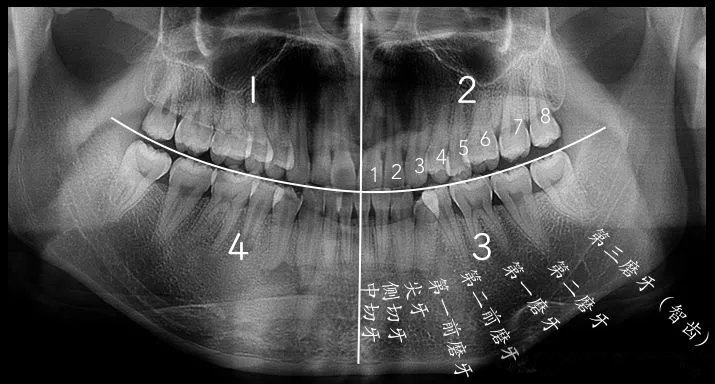

如圖所示,第8顆就是智齒

不是的,智齒雖然相比普通拔牙,因為(wei) 位置靠裏拔牙難度大一些,不過智齒通常還可以分為(wei) 上頜智齒和下頜智齒,長齊了的話,就是上下左右一共4顆。相對下頜智齒來說,大部分上頜智齒拔牙相對容易一些。而下頜智齒位置多樣,牙根情況也更複雜,拔除難度一般要大一些。